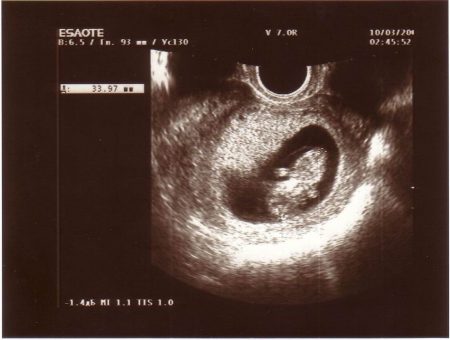

Після того як ви повідомите лікаря про тривожать вас симптомах, він призначить вам ультразвукове дослідження. Спеціаліст, який буде робити УЗД, зможе визначити стан плода, стінок матки. Крім того, можна визначити локалізацію спазму, так, він може локалізуватися на задній стінці. Не менш часто зустрічається гіпертонус передньої стінки.

Також, тонус можна діагностувати при здачі крові на кількість такого гормону, як прогестерон (що відповідає за скорочення м'язів). Найчастіше відзначається тонус матки на ранніх термінах вагітності, періодом ризику вважається: 1 - 4 тижні і 8 - 12 тижнів. Однак цей стан може виникнути у другому і навіть в третьому триместрі, періоди ризику: